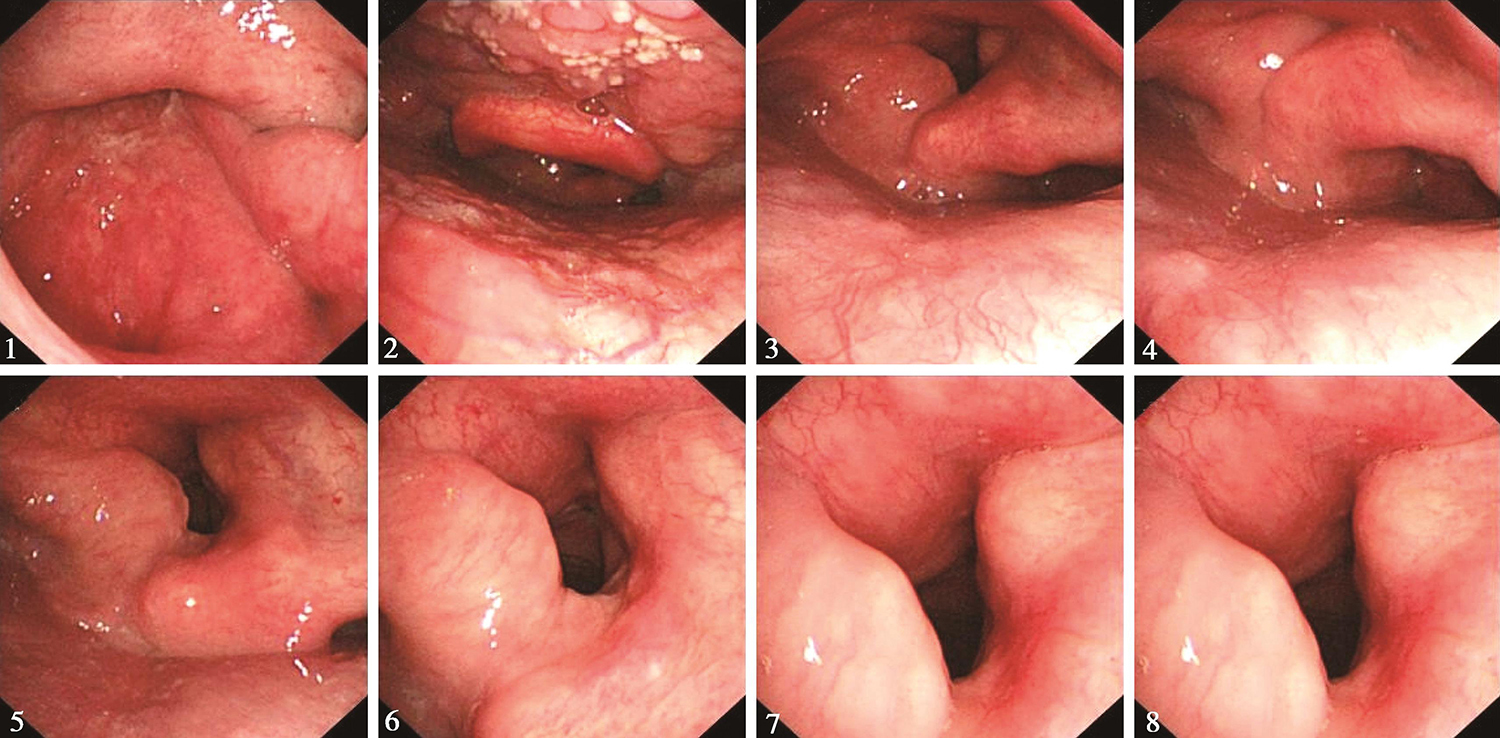

1.2015年6月11日电子鼻咽喉镜检查

鼻腔进镜顺利。鼻咽部结构完整,黏膜光滑,未见明显异常。口咽双侧扁桃体未见肿大。舌根部淋巴滤泡增生明显。下咽部表面光滑,双侧梨状窝对称,未见明显异常。喉部会厌及双侧披裂结构正常,黏膜光滑。声门区左侧声带可见粗糙不平肿物生长,左侧声带明显增厚,累及全长,向前侵及前联合,向后达声带突,向左侧喉室内生长,左侧室带前端受累及(图1)。右侧声带萎缩,表面黏膜充血,未见明显侵及。双侧声带活动未见受限。声门下未见侵及。

图1 喉镜示左侧声带肿物

1.2015年9月22日电子鼻咽喉镜检查

“喉癌术后3个月”,鼻腔进镜顺利。鼻咽部结构完整,黏膜光滑,未见明显异常。口咽双侧扁桃体未见肿大。舌根部淋巴滤泡增生明显。下咽部表面光滑,未见明显异常。喉部会厌及双侧披裂结构完整,声门区呈术后改变,双侧声带基本切除,原前联合位置可见肉芽结节(图3)。声门裂开放尚好。左右半喉活动未见明显受限。

图3 2015年9月22日复查喉镜示双侧声带基本切除,原前联合位置见肉芽结节

3.2016年2月22日电子鼻咽喉镜

“喉癌术后半年余”,鼻腔进镜顺利。鼻咽部结构完整,黏膜光滑,未见明显异常。口咽双侧扁桃体未见肿大。舌根部淋巴滤泡增生明显。下咽部表面基本平整,未见明显异常。喉部声门上结构基本完整,双侧披裂保留,黏膜充血。声门区左侧声带切除,声门区肉芽组织消退,声门区未见明确肿瘤征象(图4)。左半喉基本固定,右半喉活动尚可。

图4 2016年2月22日复查喉镜示声门区肉芽组织消退

5.2016年8月25日电子鼻咽喉镜检查

“喉癌术后1年余”,鼻腔进镜顺利。鼻咽部结构完整,黏膜光滑,未见明显异常。口咽双侧扁桃体未见肿大。舌根部淋巴滤泡增生明显。下咽部表面基本平整,未见明显异常。喉部声门上结构基本完整,双侧披裂保留,略显水肿。声门区左侧声带切除,局部基本平整,声门区未见明显肿瘤征象。左半喉基本固定,右半喉活动尚可(图5)。

图5 2016年8月25日复查喉镜示声门区未见明显肿瘤征象

9.2017年4月21日电子鼻咽喉镜

“喉癌术后2年”,鼻腔进镜顺利。鼻咽部结构完整,黏膜光滑,未见明显异常。口咽双侧扁桃体未见肿大。舌根部淋巴滤泡略增生。下咽部表面基本平整,未见明显异常。喉部声门上结构基本完整,双侧披裂保留,略显水肿。声门区左侧声带切除,局部基本平整,声门区未见明显肿瘤征象。左半喉活动度小,右半喉活动尚可(图6)。

图6 2017年4月21日复查喉镜